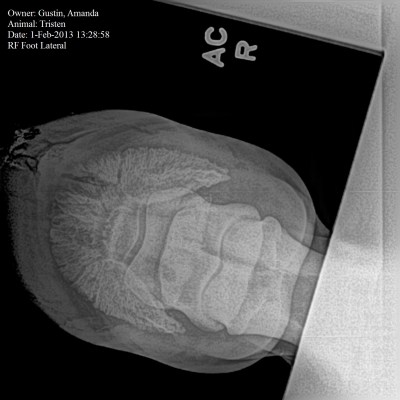

Here’s the view that made him say that. You can see the triangular fracture fragment pretty easily in this picture, as well as the irregular margins. Osteolysis is a fancy word for bony changes, which you can see between the fragment and the rest of the coffin bone. The “smaller rounded osseous fragments” are bone chips.

Long toe and concavity is something we knew we had, and that’s been present practically since day one of the abscess. The gas tracking is also due, presumably, to the massive hole of the abscess. You can see both in this side view. This view was taken before a second, more aggressive trim of the toe that we did based on the x-ray, so the long toe was corrected.